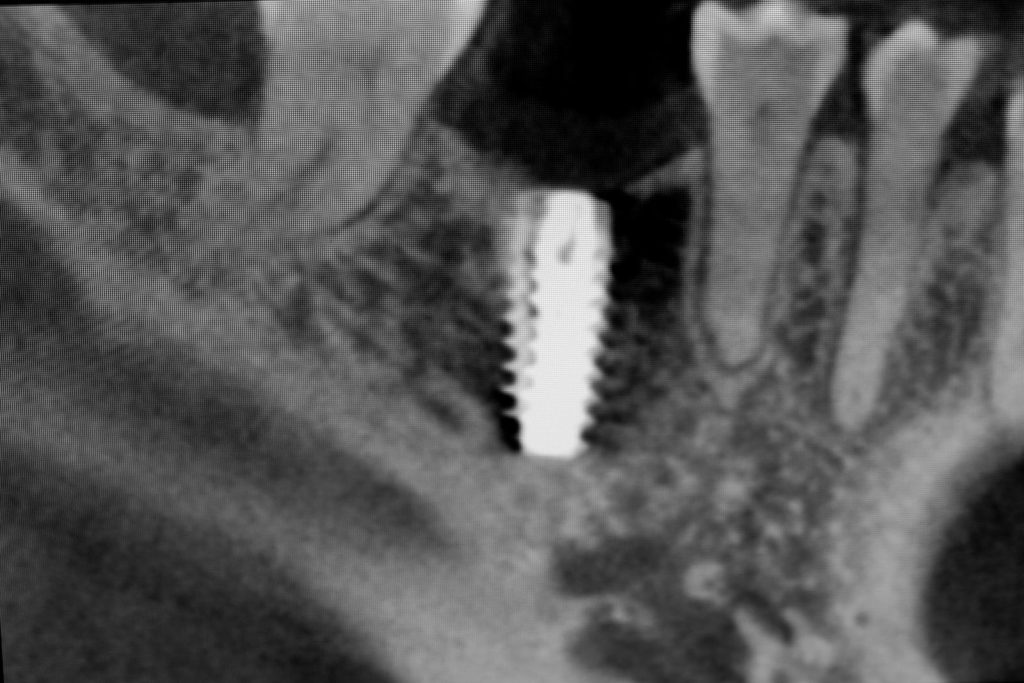

Procedury te są stosowane w sytuacji niedostatecznej ilości kości, skutkującej odsłonięciem gwintu, podczas gdy wszczepiamy implanty stomatologiczne lub też jako zabiegi poprzedzające ich wprowadzenie.​

• Metoda otwarta – opisana w 1980 przez Jamesa i Boyna – polega na chirurgicznym dostępie do zatoki szczękowej poprzez jej boczną ścianę, następnie delikatnej preparacji, oddzieleniu wyściółki (błony Schneidera) bez jej perforacji, umieszczeniu pomiędzy nią a dnem zatoki materiału odbudowującego kość. Zabieg podniesienia dna zatoki szczękowej może przebiegać z jednoczesnym wszczepieniem implantów lub wszczepieniem ich w czasie odroczonym o 6–8 miesięcy. Warunkiem jednoczesnego wszczepienia implantów jest możliwość pierwotnie stabilnego ich umocowania w pozostałej własnej kości wyrostka zębodołowego. Najmniejsza jej ilość wg niektórych autorów to 1 mm.

• Metoda zamknięta – opisana w 1994 przez Summersa – bez szerokiego otwierania zatoki szczękowej, stosowana w sytuacjach wymagających niewielkiego zakresu rekonstrukcji na wysokość. W tej metodzie materiał regeneracyjny do odbudowy kości wprowadza się przez nawiercony kanał, komunikujący się z zatoką w pozycji zaplanowanej do wszczepienia implantu, lub tylko kondensuje się (zagęszcza, rozpycha i wydłuża) obszar kości dla uzyskania stosownej jej ilości i gęstości dla stabilnego umocowania implantu. Zabieg odbudowy kostnej wg Summersa wykonuje się przy użyciu specjalnego instrumentarium – zestawu osteotomów. Uzyskuje się dodatkowo 2–4 mm kości na wysokość

Metoda rekonstrukcji kostnej w oparciu o indywidualnie drukowane siatki z tytanu dla implantacji wszczepów śródkostnych stosowana jest najczęściej jako dwuetapowa. W pierwszym etapie odbudowywana jest kość, natomiast implanty wszczepiane są po okresie 4–6 miesięcy. Na wgojenie implantów oczekujemy od 4 do 6 miesięcy w zależności od miejsca ich lokalizacji. Siatka tytanowa po spełnieniu swojej funkcji rusztowania dla odbudowującej się kości jest następnie usuwana w dniu wszczepienia implantu. Jeżeli kość spełnia odpowiednie warunki, istnieje możliwość zastosowania modyfikacji siatki tytanowej, która umożliwia jednoczesne wprowadzenie implantów wraz z odbudową kostną. Wariant ten skraca czas od pierwszego zabiegu do wykonania gotowych koron protetycznych na wprowadzonych implantach.